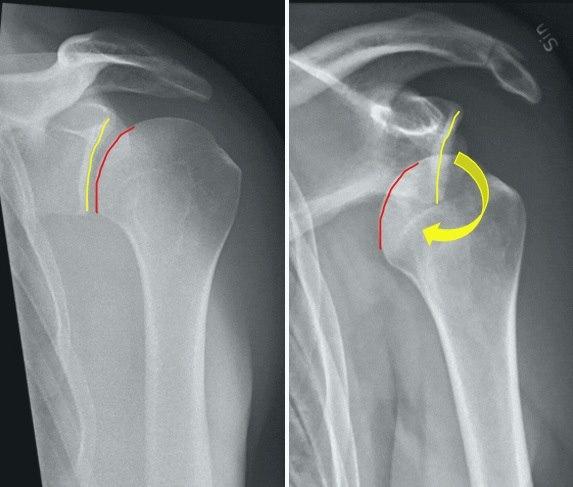

Bildet viser røntgen av normal skulder sammenliknet med bilde av skulder ute av ledd. (Donert av dr. A. Aamodt)Diagnosen er ofte lett å stille. Plutselig oppstått smerte og tap av bevegelighet etter en skade er den typiske sykehistorien. Ved skulderundersøkelsen vil det ved fremre luksasjon være et søkk i skulderbuen (den normale skulderkonturen er endret), og hodet til overarmsbeinet kan kjennes fortil i armhulen. Om mulig vil man forsøke å få skulderen på plass igjen, reponert, så snart som mulig. Det bør helst utføres røntgen før man forsøker å reponere, dette er for å utelukke f.eks. et brudd i overarmen. Forsøker man å trekke hardt i dette kan det forårsake større skade. Dersom det er lang transportvei kan man forsiktig forsøke å sette skulderen tilbake på plass (hengende arms metode).